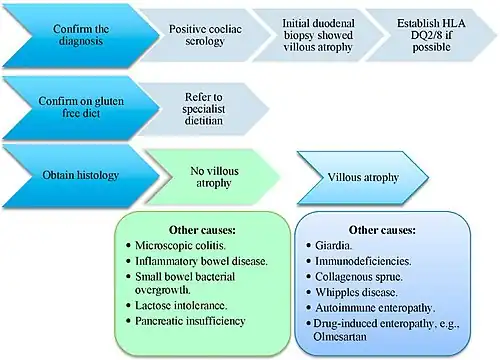

The histopathological features associated with coeliac disease can arise from other conditions as well.[57] Differential diagnosis of negative coeliac blood tests and villous atrophy or increased inter-epithelial lymphocytes includes tropical sprue, eosinophilic gastroenteritis, lactose intolerance, lymphoma, Crohn’s disease, Helicobacter pylori, drug-induced enteropathy (azathioprine, methotrexate, mycophenolate, olmesartan, colchicinenon, non-steroidal anti-inflammatory drugs, and proton pump inhibitors), whipple disease, Giardiasis, radiation enteritis, tuberculosis, Zollinger–Ellison syndrome, collagenous sprue, common variable immunodeficiency, autoimmune enteropathy, HIV enteropathy, small intestinal bacterial overgrowth, and gastrinoma with acid hypersecretion.[59][20][61][57] If the histological changes improve with a gluten free diet despite negative coeliac disease blood tests a diagnosis of seronegative coeliac disease may be made.[20]